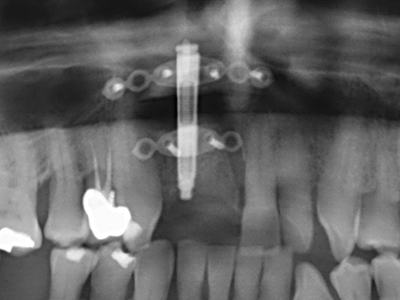

En la extracción de bloques óseos la piezocirugía también presenta ventajas adicionales: Además de la alta precisión en la osteotomía que ya se ha descrito antes, se ha comprobado que el uso de los delgados insertos de sierra resulta especialmente cuidadosas con el hueso. Frente a esto, sobre todo cuando se usan las fresas de Lindemann, cabe esperar pérdidas en la extracción significativamente más altas debido al mayor grosor de la parte frontal del cabezal (Lakshmiganthan, Gokulanathan et al. 2012). La separación basal que se necesita en particular en los injertos de bloque extraídos de forma retromolar se ve facilitada mediante sierras perpendiculares especialmente previstas a tal fin, lo que permite considerar que la cirugía piezoeléctrica es un procedimiento preciso y seguro para la obtención de bloques de hueso en el área retromolar (Happe 2007) (fig. 1-12).

Como ya se ha demostrado en el pasado, básicamente cualquier procedimiento de cirugía de hueso representa una posible indicación para la cirugía piezoeléctrica. Así, la preparación del segmento móvil en la osteogénesis de distracción (fig. 23-25) y en la osteotomía de sándwich puede realizarse con piezas especiales, sin poner en peligro el suministro sanguíneo de la parte crestal, que resulta esencial para el éxito de ambas técnicas (González-García, Diniz-Freitas et al. 2008).

Para la extracción de implantes es posible realizar la preparación de una tapa ósea vestibular que, tras retirar el tornillo del implante, vuelve a fijarse y, de este modo, mantiene el contorno de la apófisis alveolar.

En la cirugía del seno maxilar surgen otros campos de aplicación: En este punto, tras la preparación concéntrica de una tapa ósea de la pared del seno maxilar (que suele tener forma trapezoidal), es posible eliminar patologías y cuerpos extraños del seno maxilar. La tapa ósea se repone después de finalizar la parte intra-antral de la operación y se asegura frente a una posible dislocación mediante cuñas o suturas adaptables.